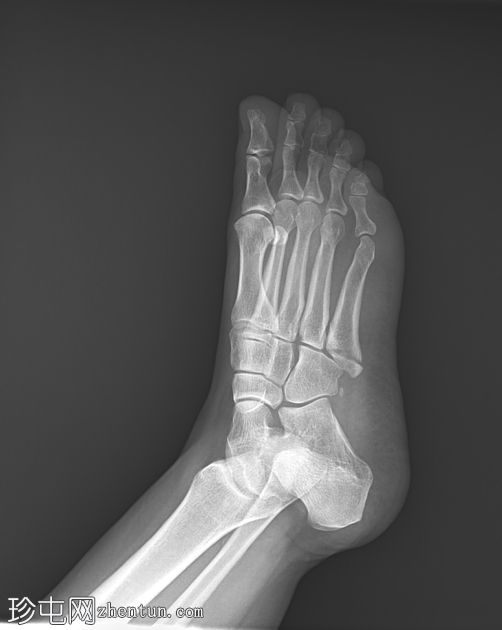

X线片

1.jpeg

正位片

可见第五跖骨基底部粗隆(茎突)骨折。骨折线位于关节外,未延伸至第四至第五跖骨间关节。移位轻微。未见其他急性骨折。偶见腓骨副骨。